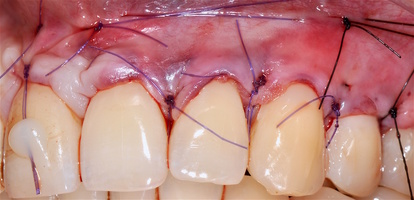

1. Генерализованные рецессии в области нижней челюсти оперировались в один этап все 12 зубов, фронтальный участок с аутотрансплантатом от 3.2 до 4.2 зубов. А дистальные участки от 3.6 до 3.3 и от 4.6 до 4.3 зубов с использованием пластического материала ТМО (dura mater) (рис. 4а-з).

4. Затем проводиться позиционирование аутотрансплантата в области рецессий и принимающего ложа двумя-тремя узловыми швами; после аутотрансплантат стабилизируют прижимающими двумя-четырьмя матрасными крестообразными швами, что позволит плотно прижать аутотрансплантат и избежать образования «мертвых» зон для питания аутотрансплантата.

4. Фиксация пластического материала ТМО (dura mater) к поверхности корней зубов в области зоны создания необходимого объема прикрепленной десны.

5. Закрытие пластического материала слизисто-надкостничным лоскутом со смещением в корональном направлении, и фиксация слизисто-надкостничного лоскута швами; дополнительная фиксация зоны перемещенных и в будущем созданных мягких тканей десны в зоне рецессии десны для стабилизации результата операции.

Деэпителизация анатомических сосочков, обработка поверхностей корней зубов, фиксация свободного десневого аутотрансплантата и пластического материала ТМО (dura mater) швами, с полным перекрытием слизисто-надкостничным лоскутом, фиксация швами слизисто-надкостничного лоскута узловыми одиночными швами в области установки аутотрансплантата и ТМО (dura mater), двойными обвивными для слизисто-надкостничного лоскута, и крестообразными прижимающими горизонтальными швами для фиксации слизисто-надкостничного лоскута в новом положении. Обработка поверхностей корней зубов проводилась аналогично.